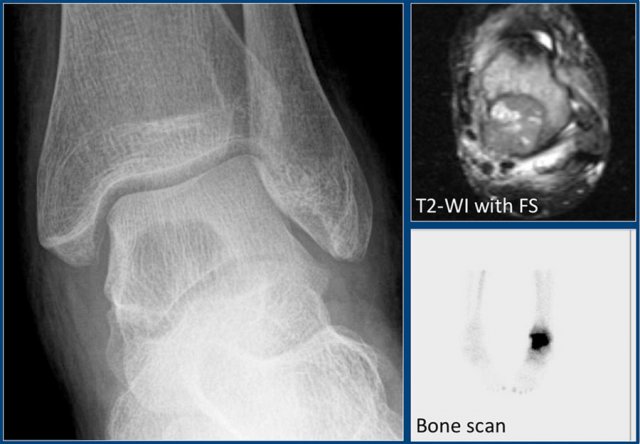

Chondroblastoma (9)

What are the findings:

• Well-defined osteolytic lesion in the talus.

• No matrix formation.

• Subtle reactive sclerosis.

• T2-WI with FS shows typical extensive peritumoral edema in the entire bone.

• High uptake on bone scintigraphy.

Diagnosis: Chondroblastoma.

The talar bone is one of the preferential sites for chondroblastoma.